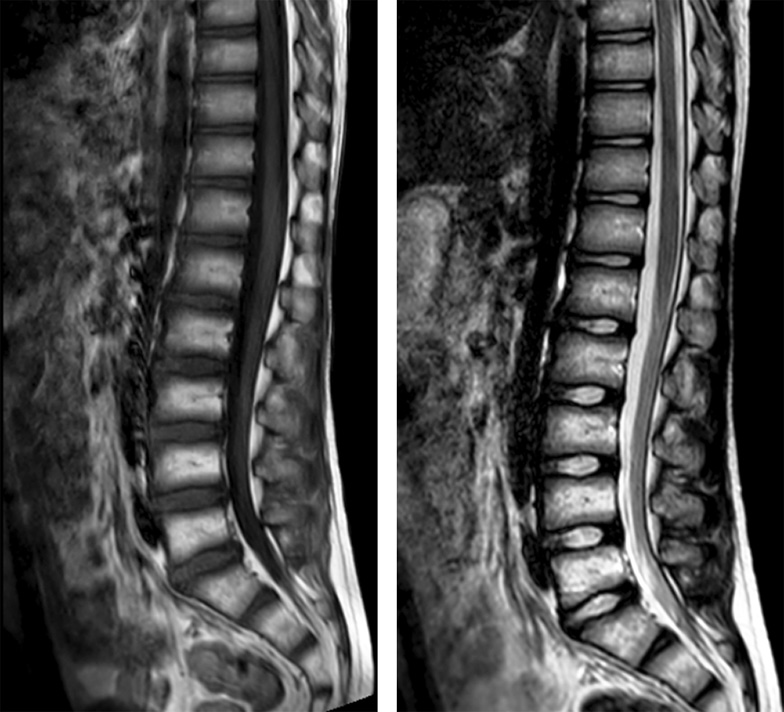

По данным лабораторных исследований клинический анализ крови, биохимический анализ крови, общий анализ мочи без патологических изменений. На компьютерной и магнитно-резонансной томограммах грудного и поясничного отделов позвоночника патологических изменений не выявлено (рис. 5, 6).

Рис. 5. Магнитно-резонансная томограмма грудного и поясничного отделов позвоночника в сагиттальной проекции, режимы Т1 ВИ, Т2 ВИ

Рис. 6. Компьютерная томограмма грудного и поясничного отделов позвоночника в сагиттальной и коронарной проекциях